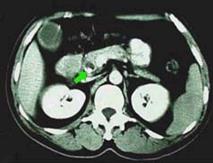

膽管擴張症的診斷可根據從幼年時開始間歇性出現的三個主要症狀,即腹痛、腹塊和黃疸來考慮。若症狀反覆出現,則診斷的可能性大為增加。囊狀型病例以腹塊為主,發病年齡較早,通過捫診結合超聲檢查, 可以作出診斷。梭狀型病例以腹痛症狀為主,除超聲檢查外,還須配以ERCP或PTC檢查,才能正確診斷。黃疸症狀在兩型間無明顯差異,均可發生。

(二)B型超聲顯像具有直視、追蹤及動態觀察等優點。如膽道梗阻而擴張時, 能正確地查出液性內容的所在和範圍,膽管擴張的程度和長度 ,其診斷正確率可達94%以上。應作為常規檢查的診斷方法。

以上各種檢查方法,在臨診時一般首先進行超聲檢查和生化測定 如臨床上捫及腹塊,則診斷即可確立, 如臨床未能捫及腫塊,而超聲檢查疑似診斷,則需進行ERCP檢查。如若受器械與年齡所限,則進行PTC檢查,必要時再輔以其他檢查方法。